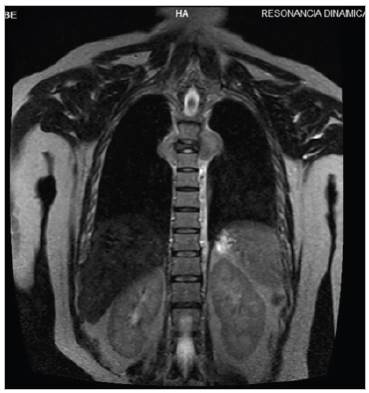

Figura 2 Resonancia magnética de columna dorsal en secuencia T2 corte coronal que muestra lesión ósea blástica en T5 que afecta cuerpo vertebral, pedículo, apófisis transversa y unión costo vertebral derecha condicionando disminución del diámetro intervertebral.